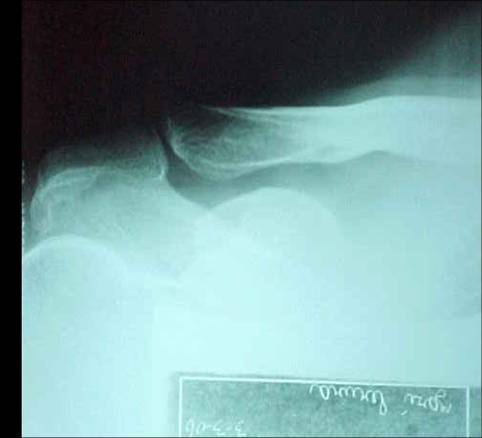

RX No. 4: Zanca

4 – Zanca (Avaliação da articulação acrômio clavicular)